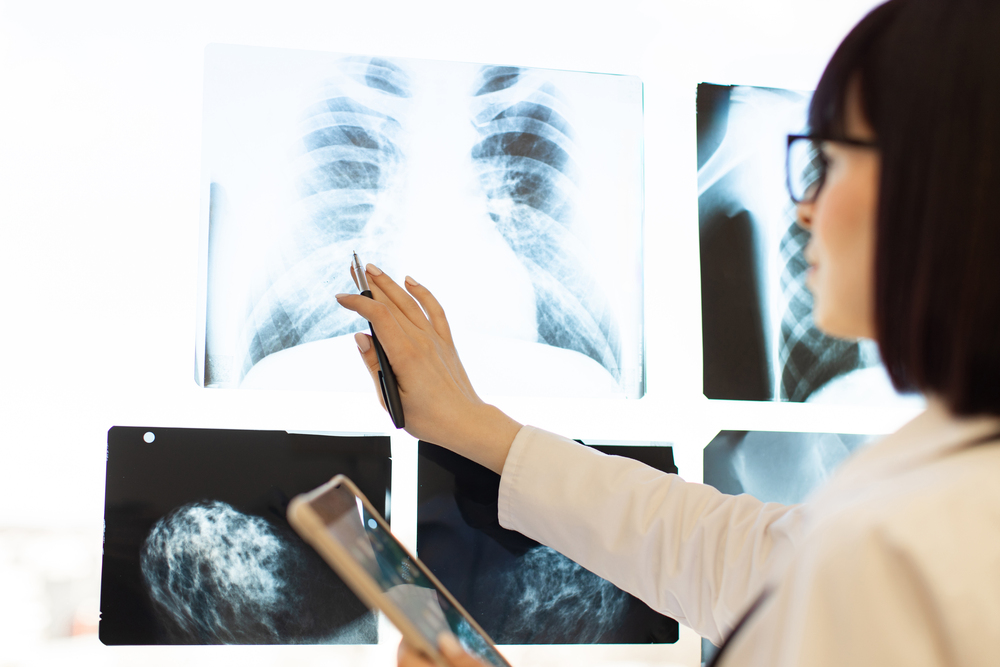

Principales Indicaciones Médicas

Los profesionales de la salud solicitan radiografías torácicas para:

- Identificar neumonía

- Detectar tuberculosis

- Evaluar fracturas costales

- Examinar tumores pulmonares

- Analizar condiciones cardíacas

- Realizar chequeos preventivos

- Efectuar evaluaciones preoperatorias

Resultados

- Disponibilidad: 24-48 horas

- Interpretación por radiólogos

- Informes detallados al médico tratante